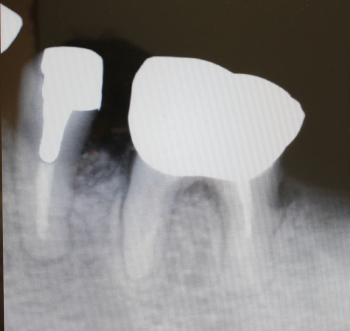

35番遠心より排膿

同部のX-ray